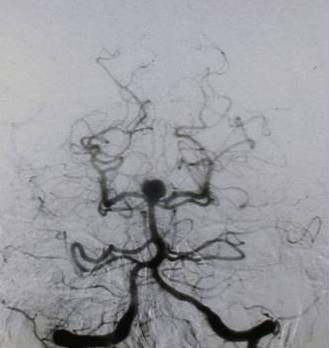

Neurovascular PageThe vascular system of the brain transporting the blood and oxygen supply weaves a web of complexity necessitating the skills of only the most expert of neurosurgeons. CU Neurosurgery has the most experienced cerebrovascular surgeon in the region on its staff, Robert E. Breeze, MD.  Under the leadership of Dr. Breeze, our multi-disciplinary program has achieved national recognition.

The Cerebrovascular Program provides a full continuum of care from emergency to rehabilitation services.  Each provider works in conjunction with members of Neurosurgery, Interventional Radiology, the Neuro-Intensive care unit, the Stroke team and Rehabilitation.  Each service is available as needed providing the most comprehensive resources in the region.

Having a team of experienced providers increases the likelihood of a positive outcome for a most delicate and complex evaluation or procedure.  It ensures that the right options and answers are provided allowing for the best decision making given the information available.  Our program defines excellence for the community.

CU Neurosurgery takes care of all types of cerebrovascular conditions. The following is a list of conditions that we typically see: